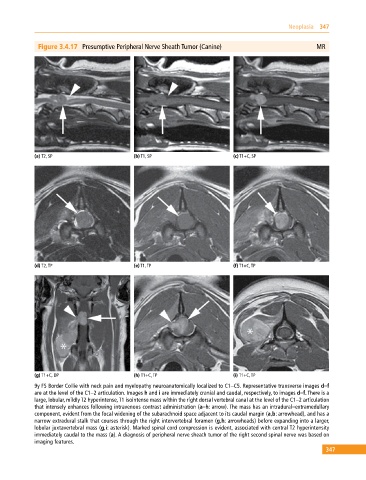

Figure 3.4.17 Presumptive Peripheral Nerve Sheath Tumor (Canine) MR

(a) T2, SP (b) T1, SP (c) T1+C, SP

(d) T2, TP (e) T1, TP (f) T1+C, TP

(g) T1+C, DP (h) T1+C, TP (i) T1+C, TP

9y FS Border Collie with neck pain and myelopathy neuroanatomically localized to C1–C5. Representative transverse images d–f

are at the level of the C1–2 articulation. Images h and i are immediately cranial and caudal, respectively, to images d–f. There is a

large, lobular, mildly T2 hyperintense, T1 isointense mass within the right dorsal vertebral canal at the level of the C1–2 articulation

that intensely enhances following intravenous contrast administration (a–h: arrow). The mass has an intradural–extramedullary

component, evident from the focal widening of the subarachnoid space adjacent to its caudal margin (a,b: arrowhead), and has a

narrow extradural stalk that courses through the right intervertebral foramen (g,h: arrowheads) before expanding into a larger,

lobular juxtavertebral mass (g,i: asterisk). Marked spinal cord compression is evident, associated with central T2 hyperintensity

immediately caudal to the mass (a). A diagnosis of peripheral nerve sheath tumor of the right second spinal nerve was based on

imaging features.